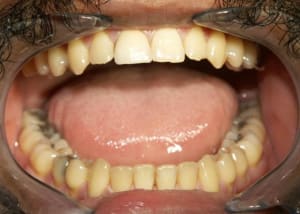

genb_kzx0m9.jpg

Voir le message contenant cette image